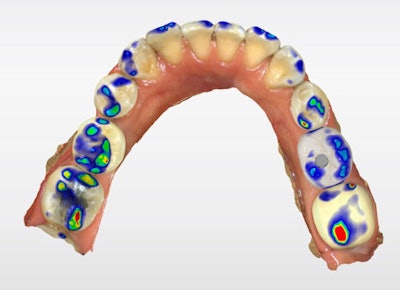

The definitive crown was then designed in CEREC software (Figure 4) using virtual articulation and occlusal analysis (Figure 5) and verified in a full-arch digital view for occlusal harmony (Figure 6). Milling was completed using CEREC Primemill with a Katana Zirconia One for Implant block, producing excellent marginal adaptation and lifelike translucency (Figure 7).

Figure 6: Full-arch digital verification.